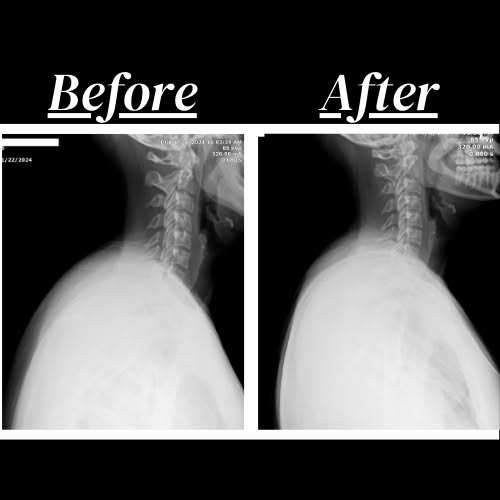

Back and neck pain ranks as the second most common reason for doctor visits (right after those pesky colds). 🤒

It’s not just a minor inconvenience.

It’s a significant problem that can disrupt daily routines and turn simple tasks into major challenges.

✅ Digital Motion Study X-rays (if medically necessary)